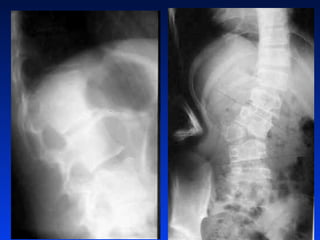

Gaõy luùn nhieàu maûnh CS

thaét löng

Gaõy luùn nhieàumaûnh CS thaét löng